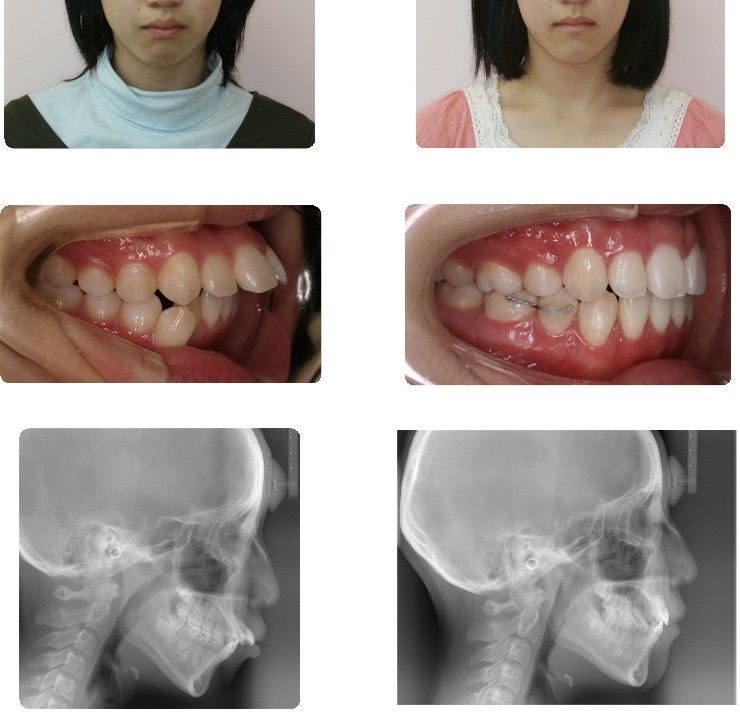

叢生(乱杭歯)

歯が大きく収まるスペースが足りないため、乱ぐい歯となっていました。

歯の本数を減らす必要がありますが、抜歯によって得られたスペースを生かし

歯列全体の歯並びと咬み合わせを正常な状態に整えることができます。